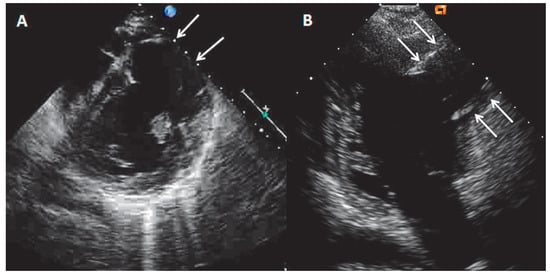

Echocardiography showed the presence of a large LV antero-lateral wall aneurysm (maximal dimensions of 57 × 41 mm) with the wall thinning resulting in the moderately depressed LV ejection fraction of 35% with preserved contractility of the remaining LV segments (Figure 1A,B, arrows). Coronary artery disease with previous silent myocardial infarction was suspected. Subsequently performed coronary angiography demonstrated normal coronary arteries.

Figure 1. Echocardiography parasternal short-axis (A) and apical two-chamber view (B) showing the presence of large left ventricular antero-lateral wall aneurysm (arrows).